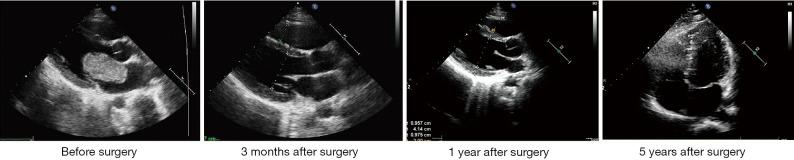

Intracranial aneurysm may appear even after the removal of the cardiac myxoma. However, the pathogenesis and treatment of such aneurysm lesions are not clear. The study aimed to explore the clinical and imaging manifestation, hypothetical pathogenesis, and therapy in one case of left atrial myxoma causing multiple intracranial aneurysms. A 14-year-old male displayed a 3-hour history of episodic loss of consciousness and right hemiplegia after a leapfrog-like movement. The myxoma was diagnosed by a combination of clinical examination, leading to the diagnosis of mitral dynamic obstruction with a Grade III mitral diastolic murmur and tumor plop; magnetic resonance imaging, revealing multiple ischemic sites in both semi-oval centers; and transthoracic echocardiography, demonstrating a mitral valve obstruction. The myxoma was removed surgically; however, computed tomography angiography showed multiple intracranial aneurysms in both middle cerebral arteries 18 months after resection of the atrial myxoma. After conservative treatment, the patient had no neurological dysfunction symptoms for 5 years after myxoma resection. His condition is relatively stable. In conclusion, resection of the atrial myxoma may eliminate the early neurological symptoms, but it cannot ensure the nonoccurrence of delayed intracranial aneurysms. The neoplastic process theory was favored for explaining the aneurysm development in this case. According to the specific conditions of the patient, a combination of open surgery, chemotherapy, radiotherapy, and coil embolization is recommended.

即使切除心脏黏液瘤后仍可能出现颅内动脉瘤。然而,此类动脉瘤病变的发病机制和治疗方法尚不清楚。本研究旨在探讨1例左心房黏液瘤导致多发颅内动脉瘤患者的临床及影像学表现、可能的发病机制和治疗方法。一名14岁男性在进行蛙跳样运动后出现3小时的发作性意识丧失和右侧偏瘫病史。通过临床检查、伴有III级二尖瓣舒张期杂音和肿瘤扑落音的二尖瓣动态梗阻诊断、磁共振成像显示双侧半卵圆中心多个缺血部位以及经胸超声心动图显示二尖瓣梗阻等综合手段确诊为黏液瘤。手术切除了黏液瘤;然而,心脏黏液瘤切除术后18个月的计算机断层扫描血管造影显示双侧大脑中动脉多发颅内动脉瘤。保守治疗后,患者在黏液瘤切除术后5年无神经功能障碍症状。其病情相对稳定。总之,切除心房黏液瘤可能消除早期神经症状,但不能确保不发生延迟性颅内动脉瘤。肿瘤形成过程理论更有利于解释该病例中动脉瘤的发生发展。根据患者的具体情况,建议采用开放手术、化疗、放疗和弹簧圈栓塞相结合的治疗方法。